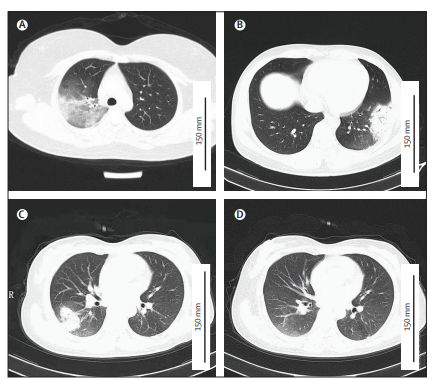

鹦鹉热衣原体(Chlamydia psittaci)是一种专性细胞内寄生、以鸟类和人为宿主的人兽共患病原体,感染人类可引起所谓的“鹦鹉热”,表现为非特异性流感样症状或社区获得性肺炎(Community-acquired pneumonia, CAP)。由于其可通过气溶胶传播,鹦鹉热衣原体被归类为潜在的生物武器。本研究对2020年底山东某医院不明病因的社区获得性肺炎疫情进行了流行病学和病原学调查,提供了鹦鹉热人传人的证据。通过整合患者流行病学和临床检测数据,研究人员确定最初6名患者为接触家禽后感染的原发病例,入院后造成多名医务人员感染,以及随后医务人员部分家庭成员感染,表明鹦鹉热衣原体可发生人际间的二代和三代传播,包括疑似无症状携带者造成的继发传播,揭示了此次疫情暴发的潜在传播链。这是中国首次关于鹦鹉热衣原体存在人际传播的报道。同时确诊了多例传染源不明的鹦鹉热患者,提示人群中存在该病原体的隐性传播风险。